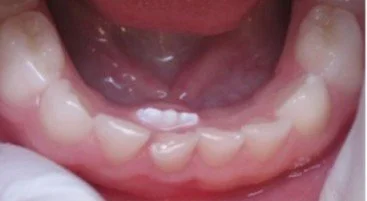

“Shark Teeth” or “Double Row of Teeth”

It’s very common for a permanent (adult) tooth to start growing behind a baby tooth—especially in the front teeth. This can look surprising, but in most cases, it’s completely normal.

Sometimes, the adult tooth comes in slightly behind the baby tooth instead. This is most common between ages 5–7, when children begin losing their first teeth.